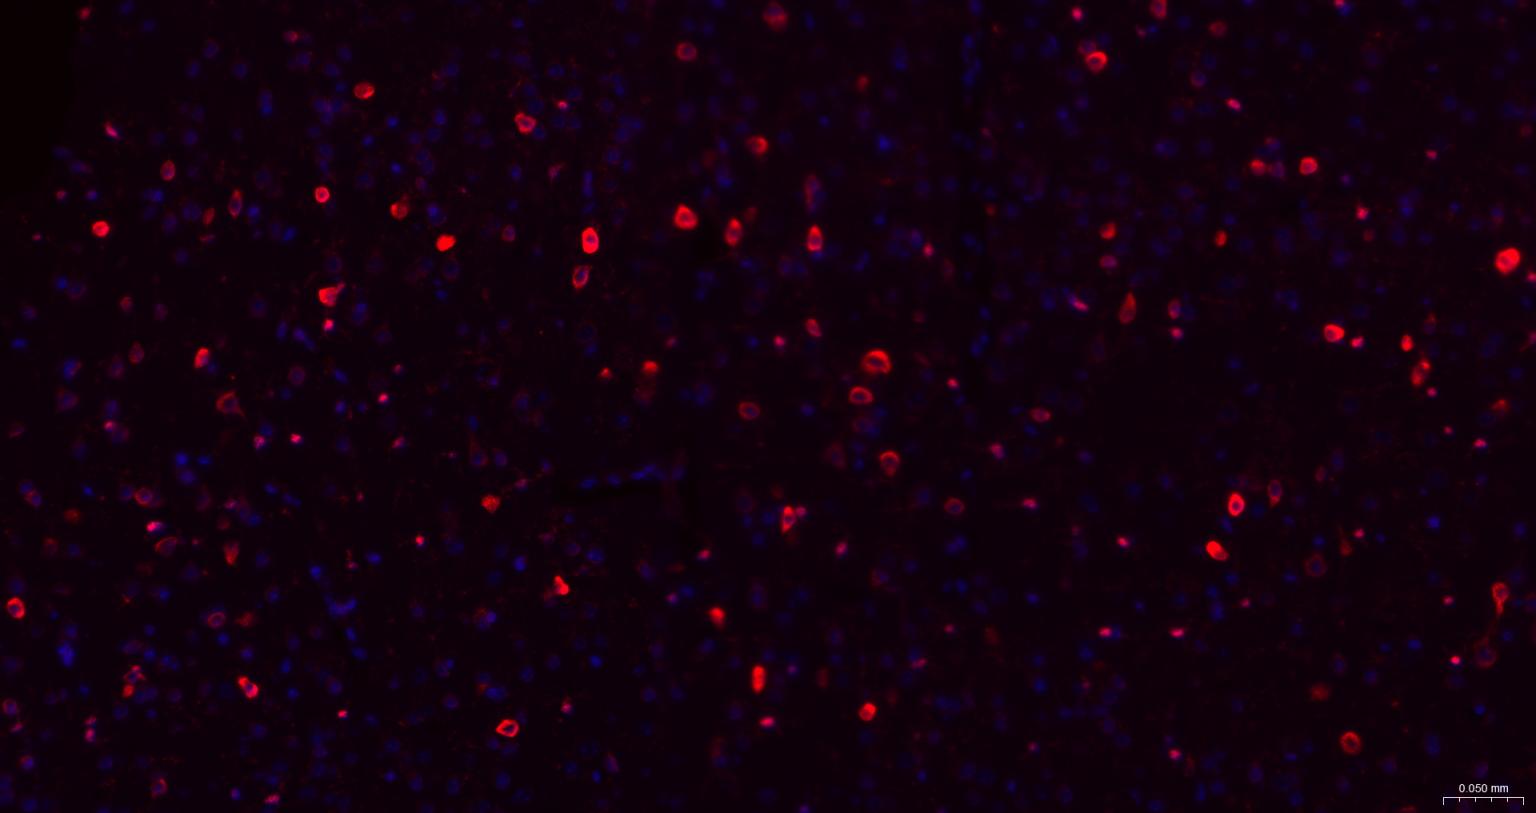

Paraformaldehyde-fixed, paraffin embedded Mouse Cerebrum; Antigen retrieval by boiling in sodium citrate buffer (pH6.0) for 15 min; The section was incubated with MSI2 Monoclonal Antibody, Unconjugated (bsm-61244R) at 1:200 overnight at 4°C. Followed by conjugated Goat Anti-Rabbit IgG antibody (Red, bs-0295G-BF594), DAPI (blue, C02-04002) was used to stain the cell nuclei.

Paraformaldehyde-fixed, paraffin embedded Rat Cerebrum; Antigen retrieval by boiling in sodium citrate buffer (pH6.0) for 15 min; The section was incubated with MSI2 Monoclonal Antibody, Unconjugated (bsm-61244R) at 1:200 overnight at 4°C. Followed by conjugated Goat Anti-Rabbit IgG antibody (Red, bs-0295G-BF594), DAPI (blue, C02-04002) was used to stain the cell nuclei.